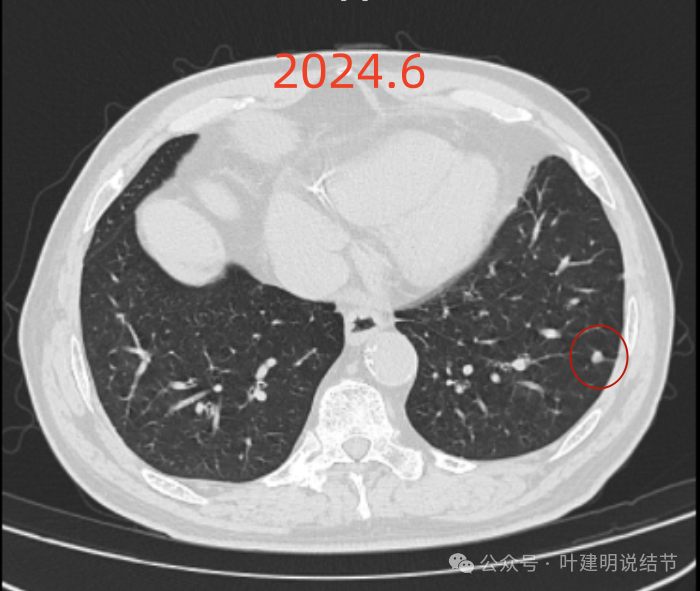

右下新增病灶,混合密度,整体轮廓较清,瘤肺边界欠清。

有小血管进入,边缘毛糙。

局部有毛刺,但不够锐利;病灶感觉有一层晕似的,邻近胸膜下也有淡磨玻璃影。

实性密度为主,周围少许很淡的磨玻璃影。

边缘不平有毛刺,但不锐利;贴着胸膜但无明显牵拉。局部表面有浅分叶似的,但总体膨胀感不够。

病灶表面不光滑,边上有晕,邻近有淡磨,贴着胸膜无牵拉。

病灶边缘欠清晰,瘤肺边界稍模糊。较宽的基底贴着胸膜。

病灶有血管进入,有浅分叶,实性为主,邻近胸膜有片状淡磨玻璃影,近胸膜无牵拉。但有一定膨胀性。

病灶实性,与血管关系较为密切。

血管走向病灶,但似乎没有被病灶影响,有向内侧的分支甚至没有哪怕一点凹向病灶侧。整体显得偏模糊。

边缘区域杂乱,边糊。